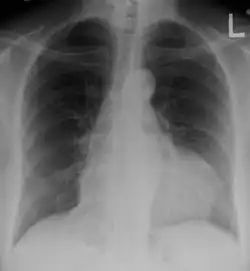

- RTG klatki piersiowej – w przypadku nagromadzenia dużej ilości płynu (ponad 250 ml) obserwuje się butelkowatą sylwetkę serca